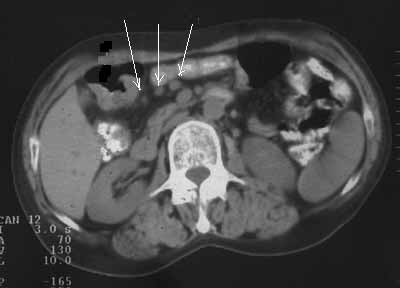

Рис. 3. Рак поперечноободочной кишки: локальное утолщение задней стенки кишки вблизи печеночного изгиба, увеличенные до 1,1 см лимфоузлы вблизи измененной кишки (стрелки).